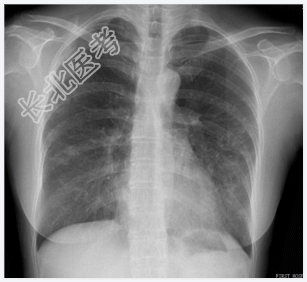

- [材料题] 患者,女性,28岁,咯血2天入院,半年前曾咯血一次。查体:双肺呼吸音粗,左下肺可闻及少许湿啰音。心脏体查无异常。做胸部X光平片检查。

- 简答题1、请问该患者诊断是什么?

- 简答题2、诊断依据是什么?

- 简答题3、鉴别诊断有那些?